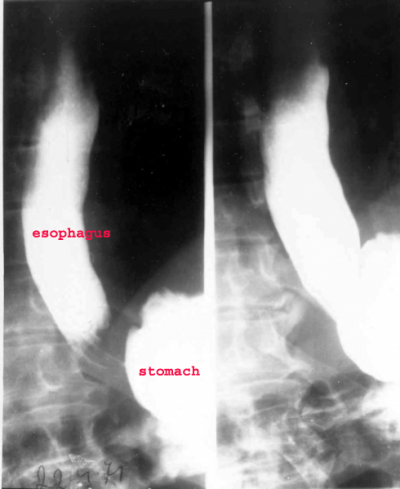

- דיספגיה. בשלבים מאוחרים יותר יווצרו היצרות של הסוגר וקיצור הוושט, בקע סרעפתי ודלקת בוושט (אזופאגיטיס). בבליעת בריום ניתן לראות הרחבה ניכרת של הוושט (תצלום 2.1).

האבחנה היא רנטגנית. לאחר בליעת בריום או CT ניתן לראות אי- סדירות של הרירית, שינון, התבלטויות על פני הרירית ולפעמים תבנית של אבני מרצפת. באזופאגוסקופיה (תצפית וושט) ניתן לראות רובדים (Plaques) לבנים-אפורים על הרירית (תצלום 2.1).